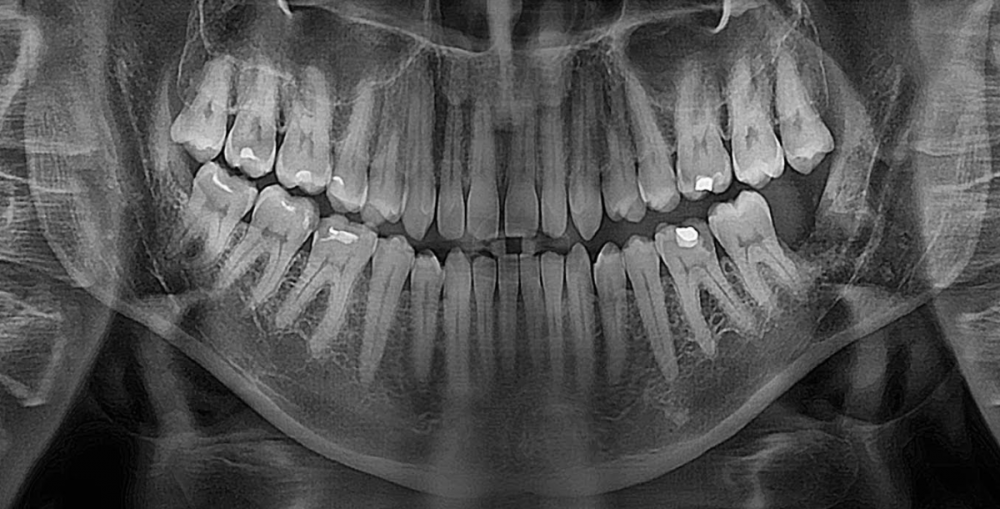

3убастик Опубликовано 27 мая, 2023 Поделиться Опубликовано 27 мая, 2023 Здравствуйте, подскажите как быть. Удалили сложную ретинированную восьмерку снизу, по причине что начала гноиться десна, зуб был в порядке. 10 дней лунка обрабатывалась ванночками из хлоргексидина после еды и еще несколько раз в промежутках. Спустя 10 дней, поняв что лунка не заживает, 10 дней в лунку закладывался левомеколь 3 раза в день на 20 минут на кусочке бинта (сам себе назначил по советам из интернета), убедившись что ничего не меняется на 23 день после удаления пошел к врачу, где был обнаружен небольшой альвеолит. Лунка была промыта хлоргексидином, врач вымыл остаток кровяного сгустка, назначил асепту, которая закладывалась в лунку по 2-3 раза в день. Через 3 дня был повторный осмотр с промыванием лунки, она оказалась чистой, продолжил закладывать асепту (14 дней), лунка особо не заживает до сих пор (сегодня 38 дней после операции и 15 дней как закладываю асепту), сделал повторный снимок, сходил еще раз на осмотр, врач сказал что стало немного получше, кюретаж не требуется, предложил продолжить до месяца использовать асепту и ждать пока затянется. В последние пару дней пару раз после закладывания асепты щипало в лунке минут по 10-15, до этого не было такого. Другой хирург посоветовал закладывать солкосерил, но меня смущает что через это лекарство может передаться болезнь Крейтцфельда-Якоба, которая аукнуться может через 5-15 лет и закончиться очень плачевно, плюс сам солкосерил сейчас стоит космических денег - за 5 г. тубу около 5 тысяч рублей. Подскажите, стоит ли использовать солкосерил, или может есть какие-то безопасные препараты для ускорения эпителизации? Прикладываю снимки до и после, плюс фото самой лунки, может кто на снимках что увидит почему не затягивается. И еще вопрос, на 7 зубе это что за вмятинка, отметил стрелкой на фото? Не может быть повреждения во время операции? Сверлили много... До удаления: После удаления: Лунка: Ссылка на комментарий

Irouil Опубликовано 27 мая, 2023 Поделиться Опубликовано 27 мая, 2023 Здравствуйте! Я предпочитаю не использовать адгезивные пасты в заживающих лунках удалённых зубов. В большинстве случаев достаточно антисептического эффекта Метрогила Дента 1-2 раза в день в лунку (на 10-15 минут и потом обязательно выполоскать/вымыть) и промывание лунки точечно (из шприца) Хлоргексидином 0,05% 2-3 раза в день Но Вы уже достаточно неуспешно позанимались самолечением, я бы не советовал повторять подобный опыт. Чтобы ответственно Вам что-то рекомендовать нужен очный осмотр P.S. не вижу ни одного признака травмы соседнего зуба в результате удаления, со стороны лунки удалённого зуба осталась нетронутая костная стенка, которая пострадала бы первой 1 Ссылка на комментарий